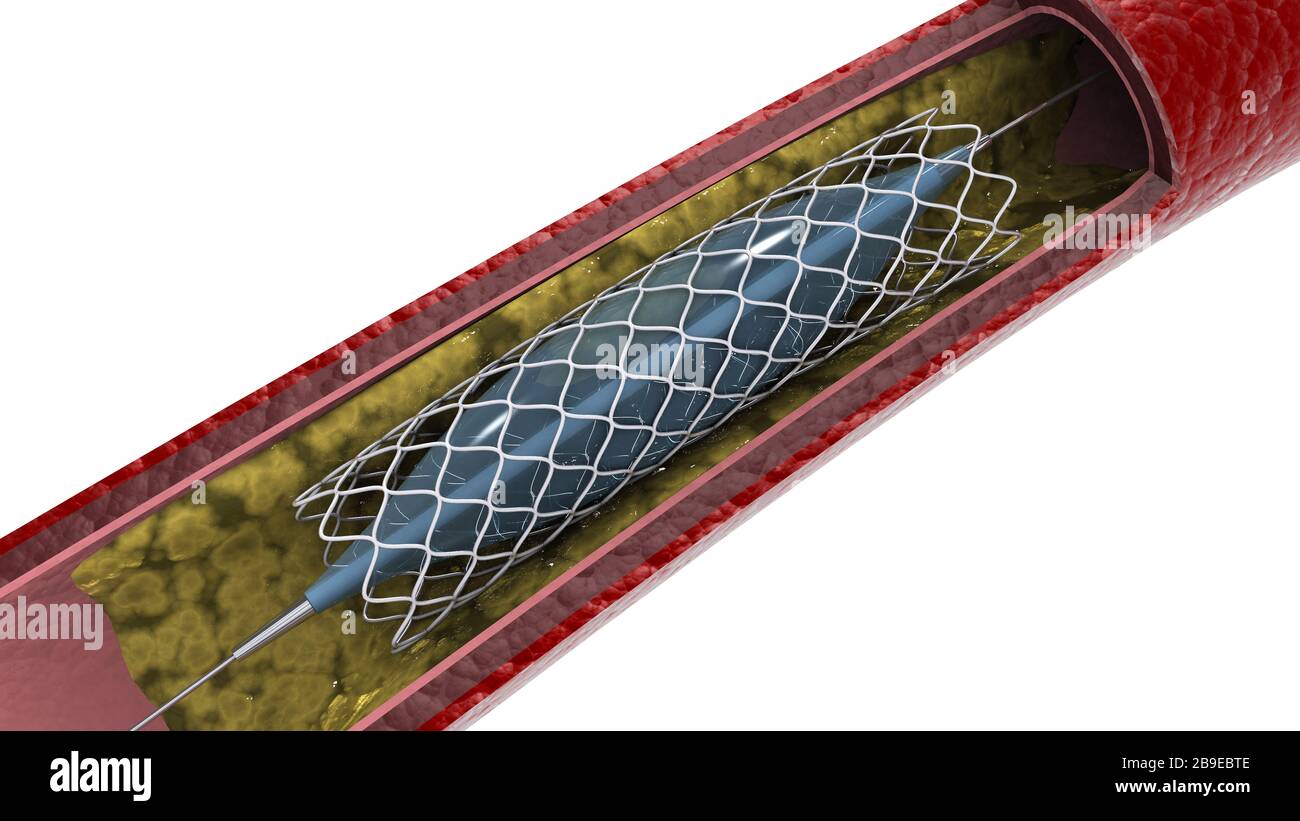

Cross-section of artery showing angioplasty and stent deployment. Stock Photohttps://www.alamy.com/image-license-details/?v=1https://www.alamy.com/cross-section-of-artery-showing-angioplasty-and-stent-deployment-image350055902.html

Cross-section of artery showing angioplasty and stent deployment. Stock Photohttps://www.alamy.com/image-license-details/?v=1https://www.alamy.com/cross-section-of-artery-showing-angioplasty-and-stent-deployment-image350055902.htmlRF2B9EBTE–Cross-section of artery showing angioplasty and stent deployment.